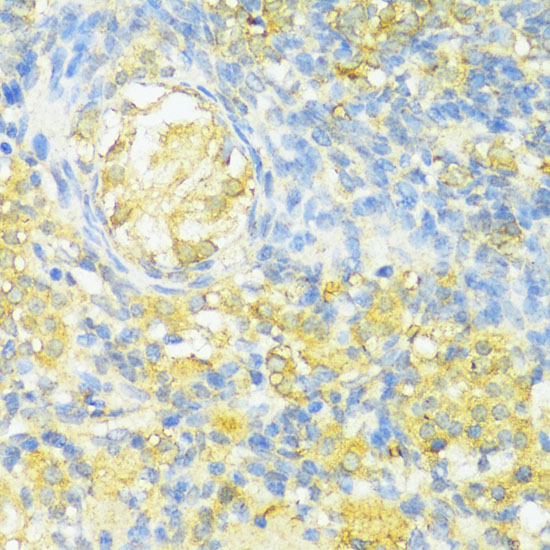

Immunohistochemistry of paraffin-embedded rat ovary using HLA-DPB1 at dilution of 1:100 (40x lens).

Immunohistochemistry of paraffin-embedded human colon carcinoma using HLA-DPB1 at dilution of 1:100 (40x lens).